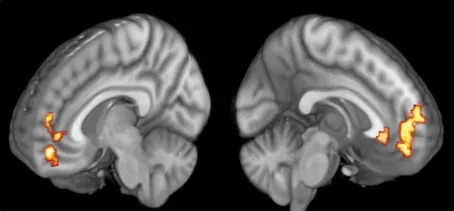

The Hidden Clues Inside a Grateful Brain (Image Credits: Wikimedia)

One of the most surprising twists in gratitude research is where in the brain the action shows up. Functional MRI studies have found that when people recall moments of sincere thankfulness, activity increases in regions tied to reward and social bonding, such as the ventral striatum and medial prefrontal cortex. These are the same territories that light up when we experience pleasure, anticipate a reward, or feel deeply connected to someone we trust. That suggests gratitude is not just a moral virtue; it is a built-in neural mechanism for tracking safety, support, and opportunity in our environment.

Researchers have also seen gratitude modulate regions associated with emotion regulation, including the anterior cingulate cortex. These areas help us shift attention away from threatening or negative cues and toward more balanced appraisals of our situation. Over time, that shift may explain why people who regularly practice gratitude report fewer symptoms of anxiety and depression. In other words, the hidden clue is not only that gratitude feels good in the moment, but that it teaches the brain to become better at managing emotional storms before they spiral out of control.